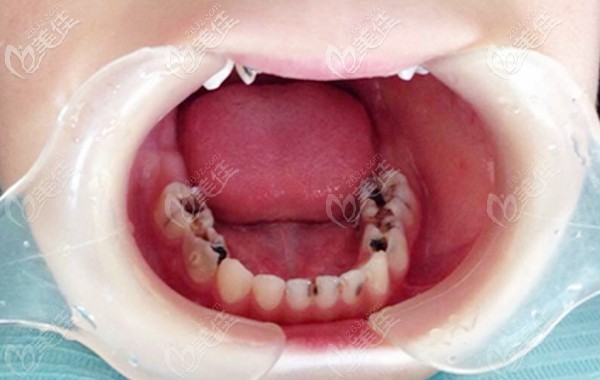

五六歲兒童乳牙齲齒需要盡快治療嗎?這些利弊你一定要知道!

五六歲兒童乳牙齲齒需要盡快治療嗎?當然了,因為不及時治療乳牙齲壞很容易壞到牙髓腔,影響恒牙萌出,導致牙齒擁擠不起,這些弊端大家一定要明白!